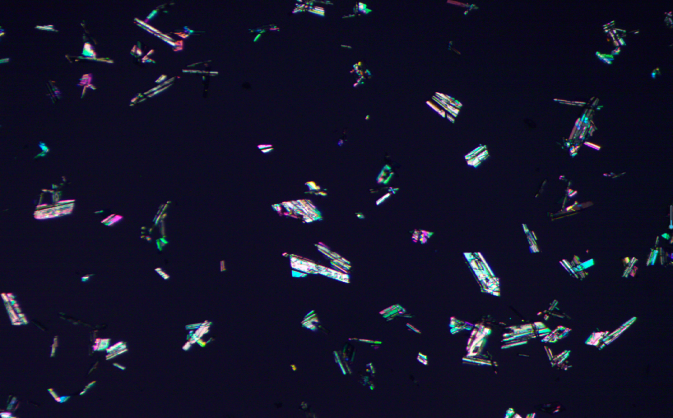

5.可以分析偏光下,偏光顆粒的粒度,粒形分析;